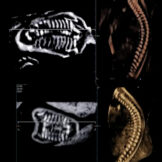

La caratteristica della tecnologia tridimensionale consiste nel fatto che non si lavora su un piano ma su un volume. Pertanto è possibile non solo, esaminare un determinato distretto nelle tre dimensioni, ma di manipolare sui tre piani il volume immagazzinato, consentendo di mettere in evidenza strutture anatomiche altrimenti difficilmente evidenziabili. Pertanto il 3D e il 4D non viene utilizzato esclusivamente per visualizzare il visino del feto* e le parti superficiali come le mani e i piedi ma per studiare il cervello (neurosonografia)**, l’apparato scheletrico *** e quello cardiocircolatorio****.